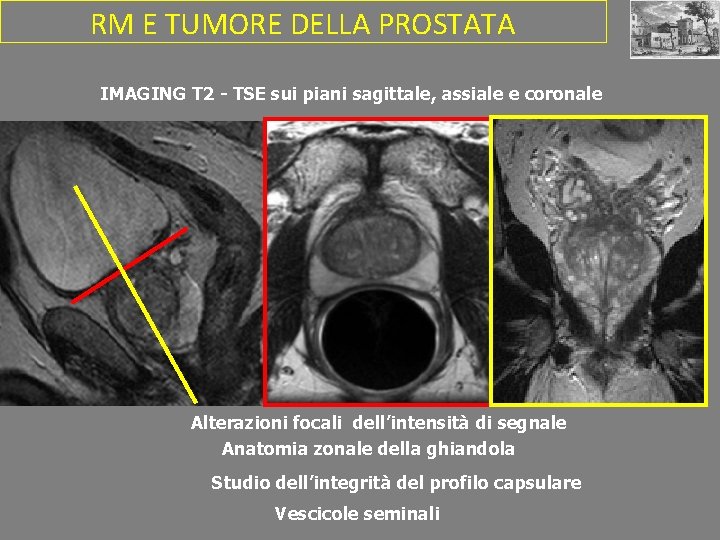

RM E TUMORE DELLA PROSTATA IMAGING T 2 - TSE sui piani sagittale, assiale e coronale Alterazioni focali dell’intensità di segnale Anatomia zonale della ghiandola Studio dell’integrità del profilo capsulare Vescicole seminali